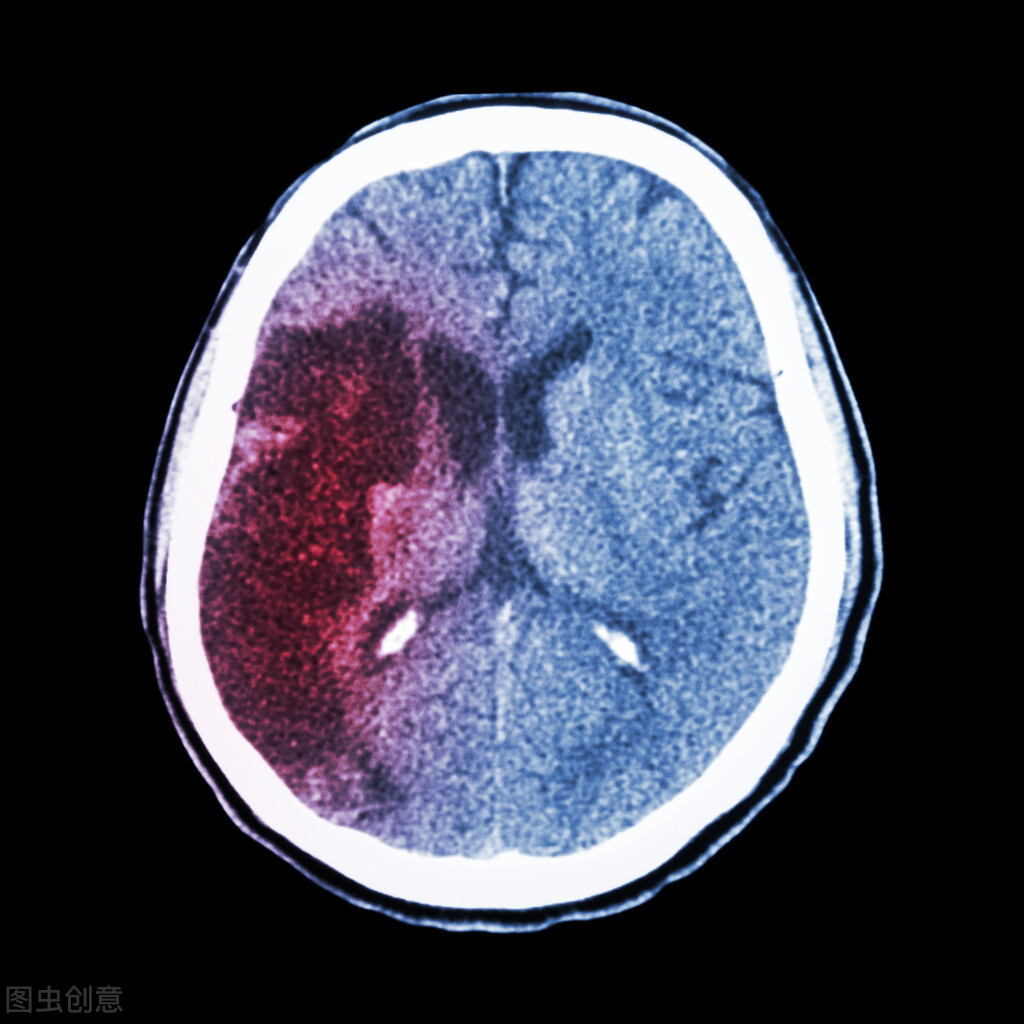

烟雾病的危害主要表现为脑梗和脑出血。由于某种原因,大脑中的大血管发生闭塞,血液不能流到大脑,导致脑梗。大血管闭塞,周围会长出许多代偿的小血管,这些小血管脆弱易破裂,导致脑出血。

实际上,烟雾病本身不会致死,但是烟雾病引起的脑梗和脑出血会致死。烟雾病长时间拖着不治,会引起脑出血和大面积的脑梗。这时候患者可能会出现生命危险。